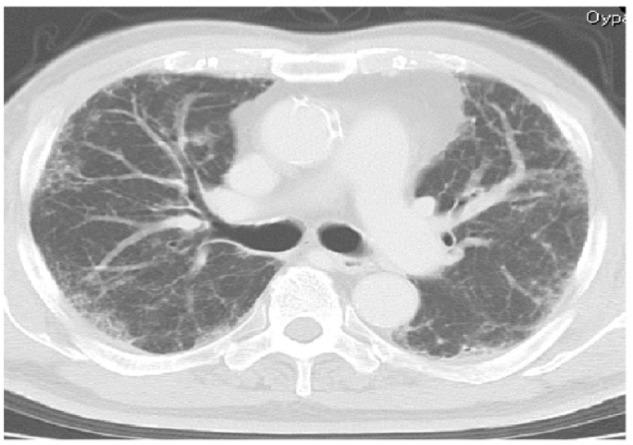

We report a case involving an 83-year-old man with interstitial lung disease who developed atypical pneumomediastinum caused by gas replacement of diminished fat. The patient presented with a complaint of worsening symptoms of respiratory difficulty since a diagnosis of chronic eosinophilic pneumonia 5 months back. He had been under observation with no particular treatment for 5 months. Computed tomography performed on admission revealed pneumomediastinum. When the current scan was compared with that obtained 5 months ago, it was evident that the fat surrounding the mediastinum had been replaced by gas density. There was no mediastinal enlargement, pneumothorax, or pneumopericardium. Because the patient was elderly, home oxygen therapy was initiated for the interstitial pneumonia with no steroid therapy. Computed tomography performed 10 months after discharge showed the reappearance of mediastinal fat and no evidence of gas density. This case is unique because the pneumomediastinum was distinct from spontaneous pneumomediastinum caused by alveolar air leaks and resembled the vacuum phenomenon caused by intervertebral disc degeneration.